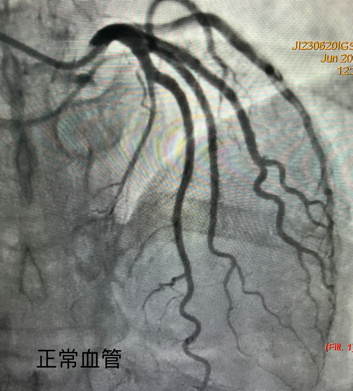

同样是做心脏介入手术,为什么有的患者需要分成多次进行介入治疗?难道不可以一次性解决吗?首先我们需要了解冠脉的组成,冠脉由左冠状动脉和右冠状动脉组成,其中左冠又分为两支前降支和回旋支。冠状动脉介入治疗需要做几次很大程度上是由患者的病变来决定的,一般的冠心病只需要一次介入治疗,可以达到血运重建,但是,对于多支血管病变,或者复杂病变就可能需要多次手术才能达到血运重建的目的。